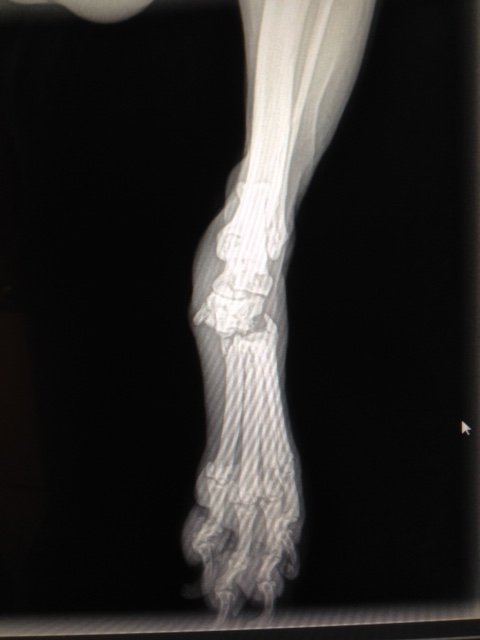

He's super cute! I have 3 cavs and they are wonderful little dogs.I added a third dog to my household right before Christmas, (which I swore I'd never do), but he fell into my lap and I could not refuse, and I couldn't be happier! He was surrendered at our clinic early December by a very sketchy guy who said his friend gave him to him because his girlfriend had just gone to jail for 10 years and he didn't want him. The sketchy man, who lives in a storage unit with 2 other dogs fyi, brought him in because he didn't want him either and oh by the way something's wrong with his leg but he doesn't know what happened....uh huh. Anyway, his leg is super broken in a crazy weird way and would be 5,000 to fix at the friends/family rate at our local orthopedic clinic (which our Practice Owner said, "He's going to be a very cute tripod!"). Oh and this guy had no idea what breed he was, he wrote long-eared beagle on his intake form (he's a Cavalier King Charles), which is probably for the best or he would have sold him straight upon getting him!

ANYWAY my parents had Cavs as I was growing up, I've always wanted one but would never pay 1400 to a breeder for a dog, I'm only rescuing (not judging, but its just not something I'm comfortable doing!), so I thought I'd never get one. And I've had a thing for 3-legged dogs for years.

So the two things just rolled into one walked into my clinic and I claimed him within 15 seconds of him being brought back as "our new dog". He's so sweet and loving and gets along with my other dogs, who are very difficult to please, and its just wonderful! 🙂)))))

View attachment 199407 View attachment 199406